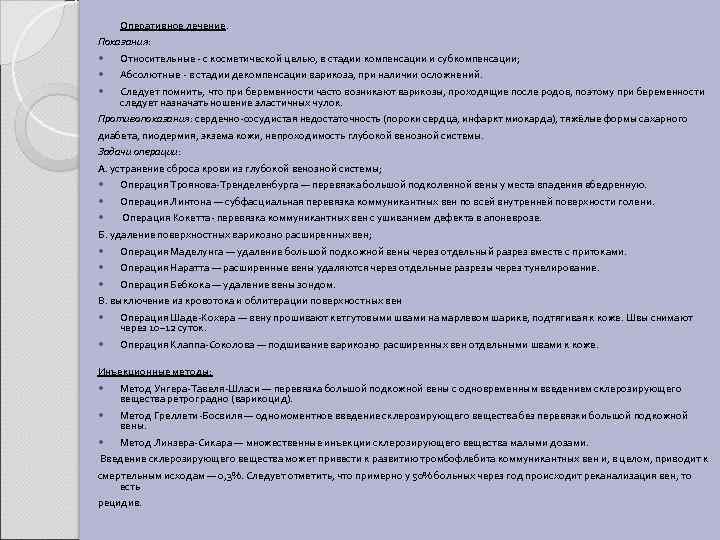

Оперативное лечение. Показания: Относительные - с косметической целью, в стадии компенсации и субкомпенсации; Абсолютные - в стадии декомпенсации варикоза, при наличии осложнений. Следует помнить, что при беременности часто возникают варикозы, проходящие после родов, поэтому при беременности следует назначать ношение эластичных чулок. Противопоказания: сердечно-сосудистая недостаточность (пороки сердца, инфаркт миокарда), тяжёлые формы сахарного диабета, пиодермия, экзема кожи, непроходимость глубокой венозной системы. Задачи операции: А. устранение сброса крови из глубокой венозной системы; Операция Троянова-Тренделенбурга — перевязка большой подколенной вены у места впадения вбедренную. Операция Линтона — субфасциальная перевязка коммуникантных вен по всей внутренней поверхности голени. Операция Кокетта- перевязка коммуникантных вен с ушиванием дефекта в апоневрозе. Б. удаление поверхностных варикозно расширенных вен; Операция Маделунга — удаление большой подкожной вены через отдельный разрез вместе с притоками. Операция Наратта — расширенные вены удаляются через отдельные разрезы через тунелирование. Операция Бебкока — удаление вены зондом. В. выключение из кровотока и облитерации поверхностных вен Операция Шаде-Кохера — вену прошивают кетгутовыми швами на марлевом шарике, подтягивая к коже. Швы снимают через 10– 12 суток. Операция Клаппа-Соколова — подшивание варикозно расширенных вен отдельными швами к коже. Инъекционные методы: Метод Унгера-Тавеля-Шласи — перевязка большой подкожной вены с одновременным введением склерозирующего вещества ретроградно (варикоцид). Метод Греллети-Босвиля — одномоментное введение склерозирующего вещества без перевязки большой подкожной вены. Метод Линзера-Сикара — множественные инъекции склерозирующего вещества малыми дозами. Введение склерозирующего вещества может привести к развитию тромбофлебита коммуникантных вен и, в целом, приводит к смертельным исходам — 0, 3%. Следует отметить, что примерно у 50% больных через год происходит реканализация вен, то есть рецидив.